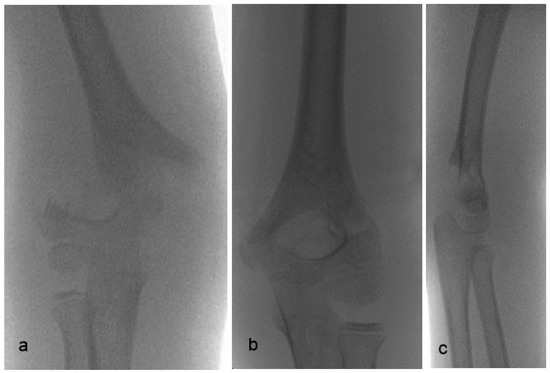

Intraoperatively, the main feature of the supracondylar humeral fracture with sideward displacement is gross instability, suggesting discontinuity of all cortices as well as a tear of the anterior and posterior periosteum. Elbow flexion during the reduction maneuver fails to control rotation (Figure 7a) as well as the sideward displacement. Moreover, flexion usually exacerbates the fracture displacement, leading to an anterior translation or flexion of the distal fragment (Figure 7b).

Figure 7. Elbow flexion during reduction maneuver: (a) fails to control rotation, (b) may convert the fracture into flexion type.